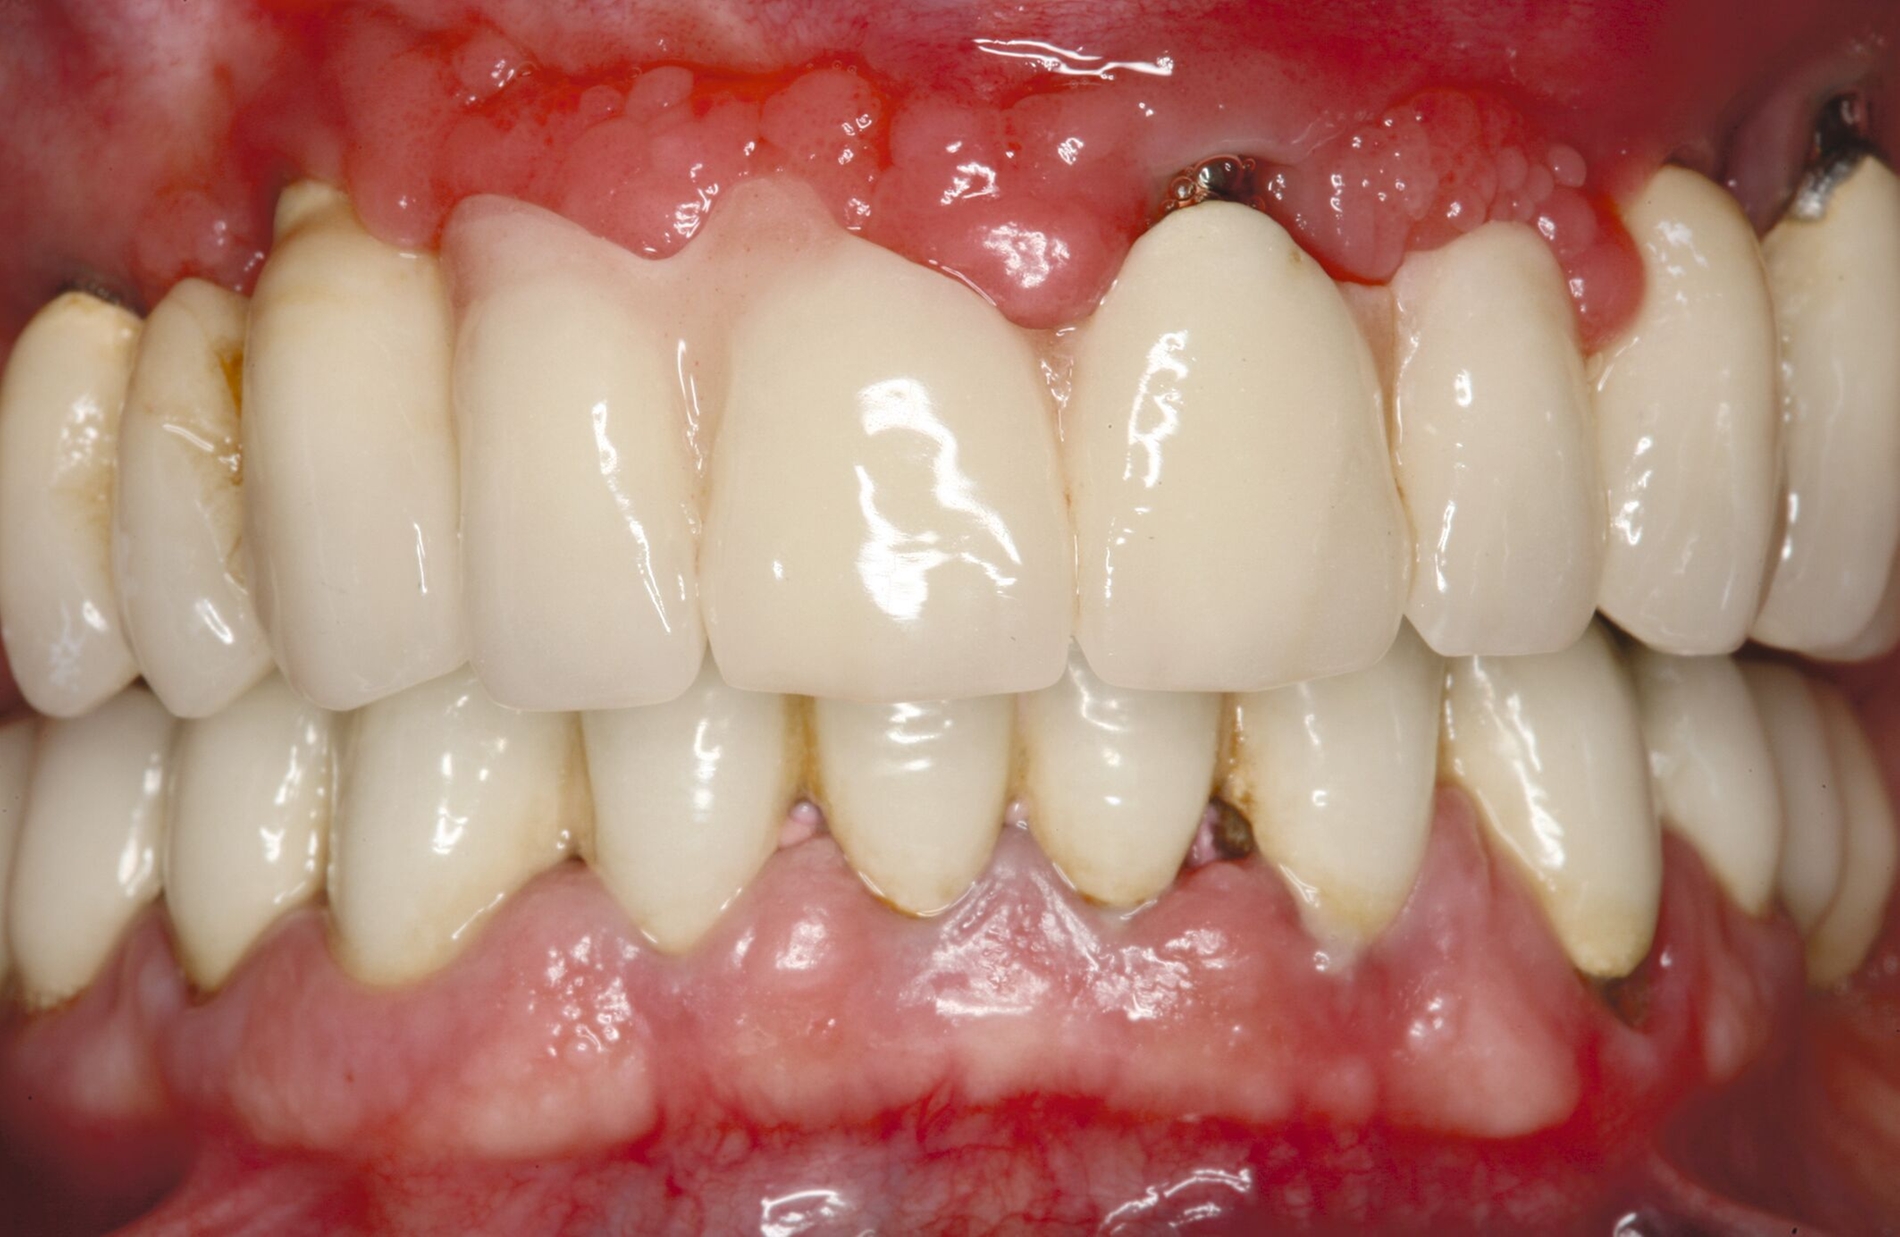

Es stellt sich die Frage, ob Implantatversorgungen zukünftigen geriatrischen Problemen mit zunehmendem Alter Rechnung tragen müssen und können. Der Wunsch nach aufwendigem (festsitzendem) Zahnersatz kann natürlich auch Älteren nicht verwehrt werden. Zudem zeigen Literaturrecherchen, dass ein fortgeschrittenes Alter und Allgemeinerkrankungen das Risiko für Implantatverluste nicht erhöhen [Schimmel et al., 2018; Srinivasan et al., 2017]. Festsitzender Zahnersatz auf Implantaten muss zuallererst hygienefähig sein, das heißt zugänglich für Zahnbürste, Interdentalraumbürstchen sowie die natürliche Spülwirkung des Speichels. Die Realität sieht manchmal allerdings anders aus (Abbildung 6).

Herausnehmbarer Zahnersatz oder eine bedingte Abnehmbarkeit von festsitzendem Zahnersatz kann nicht nur die Hygiene erleichtern, sondern erst dadurch sind Reparaturen, Erweiterungen oder spätere Umwandlungen der Suprakonstruktionen unkompliziert möglich. Bedingt abnehmbar sind nicht nur verschraubte, sondern auch provisorisch oder „semi-definitiv“ zementierte Brücken. Werden Zähne in Verbundbrücken einbezogen, sollten die natürlichen Stümpfe mit einem definitiv zementierten Käppchen aus Metall oder Keramik geschützt werden [Mundt et al., 2012]. Umfangreiche Reviews zeigen, dass biologische und technische Komplikationen auch bei festsitzenden Suprakonstruktionen keine seltenen Ereignisse sind, obwohl generell herausnehmbare Prothesen mehr Nachsorge erfordern [Jung et al., 2012; Pjetursson et al., 2012; Pjetursson et al., 2018]. Zudem ist eine effektive Periimplantitistherapie nach Kronen- beziehungsweise Brückenabnahme viel einfacher. Bei Zahn- oder Implantatverlusten können Brücken entfernt und manchmal sogar unter ihrem Erhalt umgewandelt werden. Bei manuellen oder visuellen Einschränkungen, bei großen Knochendefiziten und im parodontal vorgeschädigten Gebiss sollten die Patienten auf abnehmbare Konstruktionen gelenkt werden.